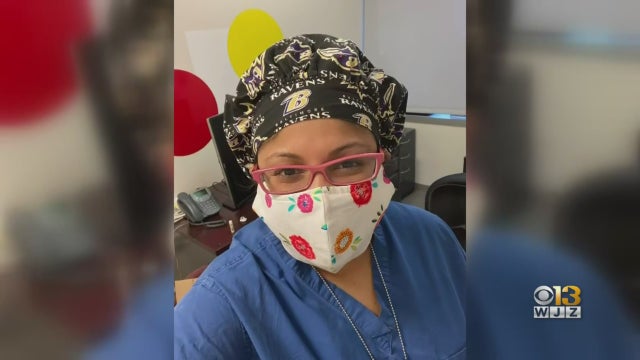

A Baltimore pediatrician is back at work treating coronavirus patients after beating the virus herself.